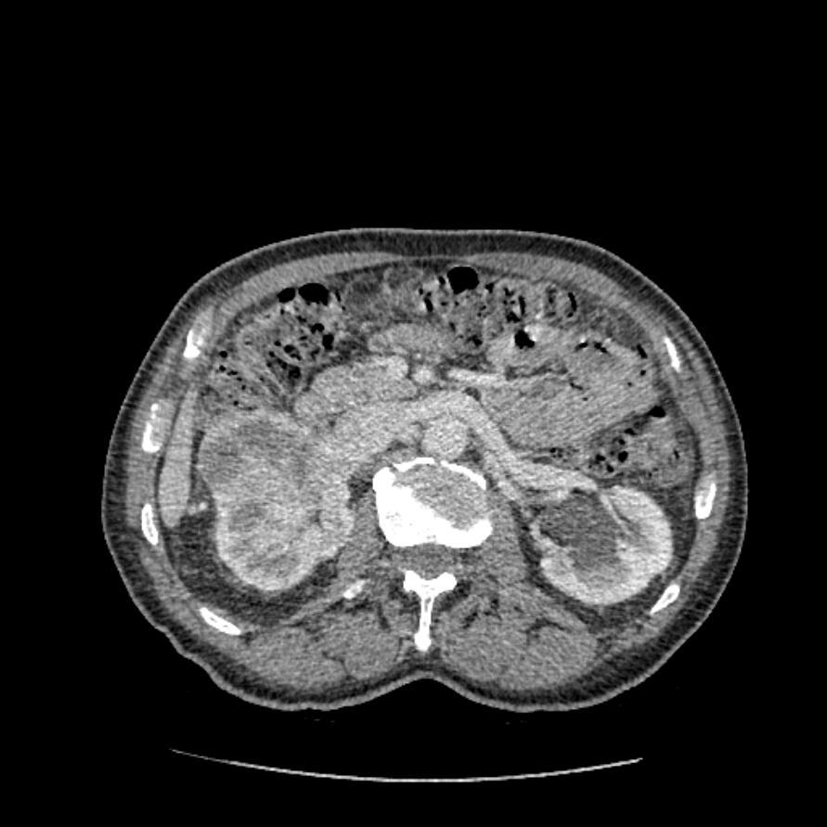

Diagnostic? Quelle maladie héréditaire peut être en cause?

Tumeurs rénales bilatérales; possible syndrome de Von Hippel Lindau